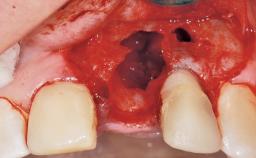

Immediate Flapless Placement of an Implant in a Maxillary Left Central Incisor Site

Pedro Tortamano, Luiz Otávio Alves Camargo

A 42-year-old female patient was referred to our clinic at the School of Dentistry of the University of São Paulo in November 2004, presenting a deficient restoration in the upper left central incisor. The clinical examination revealed no gingival retraction or any signs of gingival inflammation and, therefore, previous periodontal treatment was not considered. The patient presented a high lip line at full smile and a thin tissue biotype. This combination characterized a high-risk situation from an anatomic point of view, which required careful preoperative planning and cautious surgical execution.